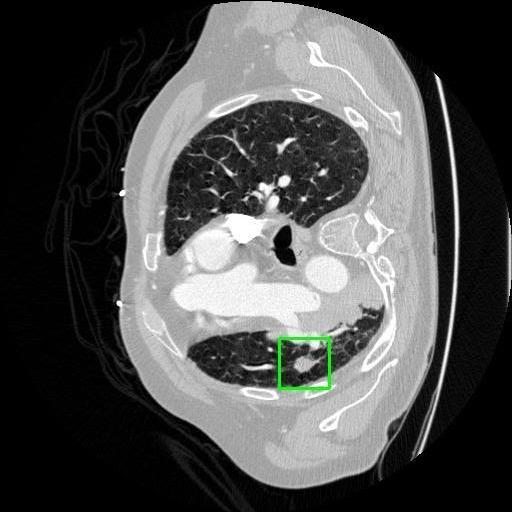

We developed an AI-based system using deep learning models for analyzing lung CT scans to detect and classify pulmonary nodules. We chose the YOLOv11 architecture for its enhanced object detection capability and adapted it specifically for medical imaging, incorporating pixel-level precision and severity classification.

Classification into three severity levels with colored bounding boxes.

Designed a severity classification system that categorizes nodules into null, moderate, and severe using colored bounding boxes, assisting in rapid clinical decision-making.